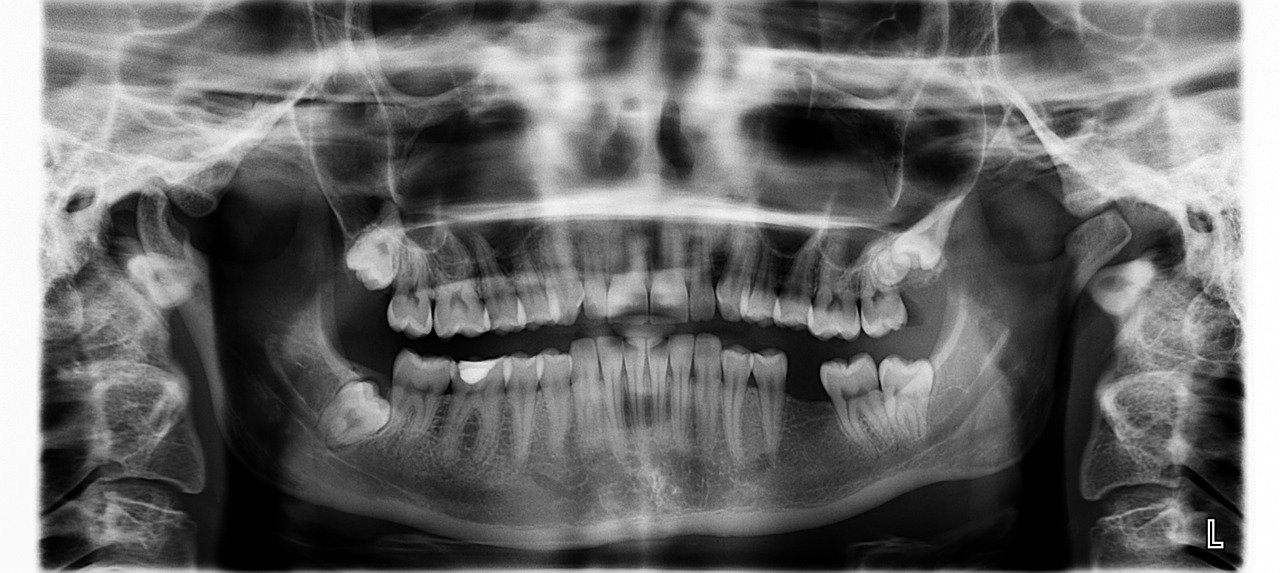

Mengenal gigi bungsu yang biasanya muncul belakangan. Mengapa ia datang 'terlambat'? Mengapa pula kalau datang bikin sakit?